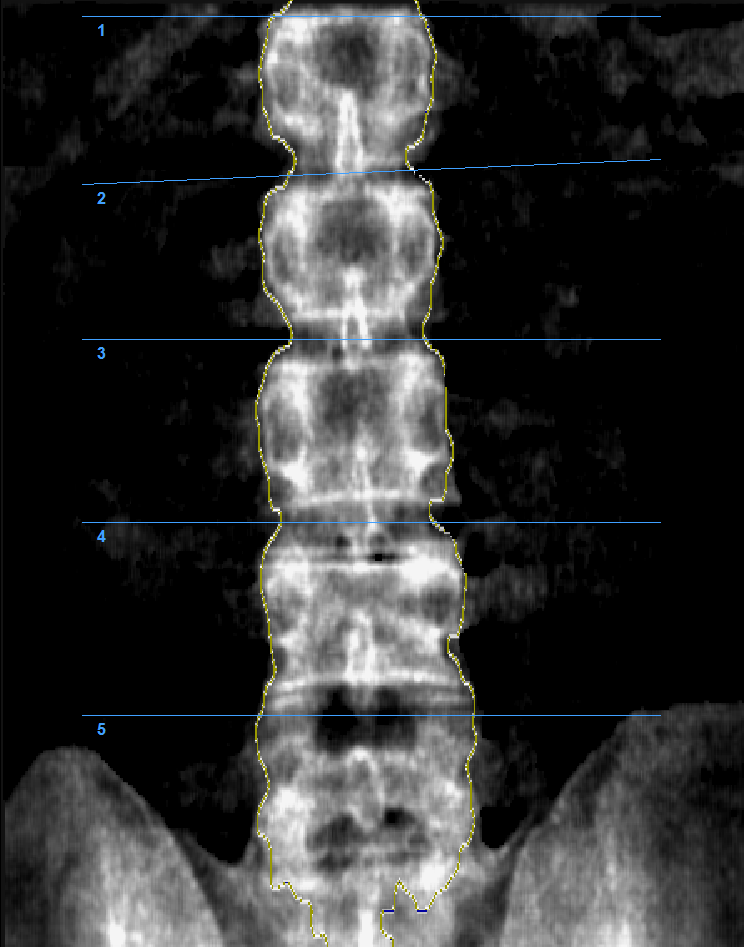

Денситометры